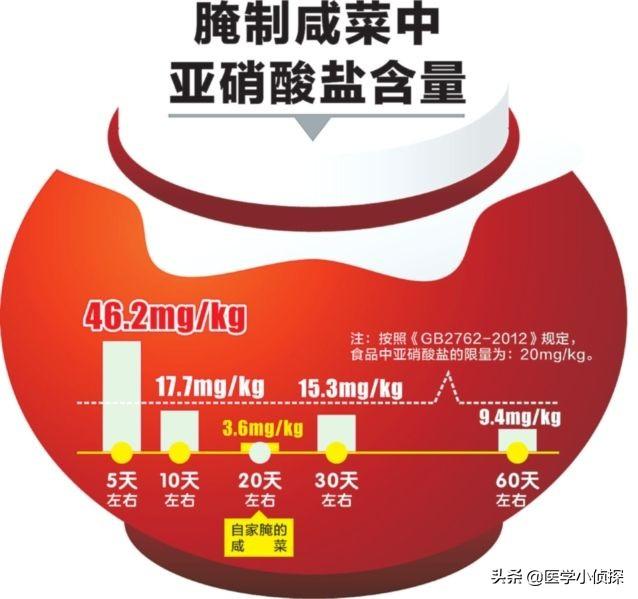

それから食生活の要素もある。新鮮な野菜や果物をより多く食べれば胃がんの発生率を減らすことができる、と私たちは言うが、同じ研究によれば、カビの生えた食品、塩漬け野菜、漬物、燻製などの常食や塩分の過剰摂取も胃がんの可能性を高めることが分かっている。私たちが言ったように、食べることが大好きな家族もいる。一般的に硝酸塩を多く含む漬物類そしてこの硝酸塩は、胃の中の細菌によって亜硝酸塩に還元され、さらに私たちの胃の中の細菌によって亜硝酸塩に還元され、アミンと結合して発ガン性物質のニトロソアミンを生成する。

- キムチ、漬物、残飯、缶詰、飲料など、自分たちの醸造によって汚染されたあらゆる種類のものを常食しているかどうか;